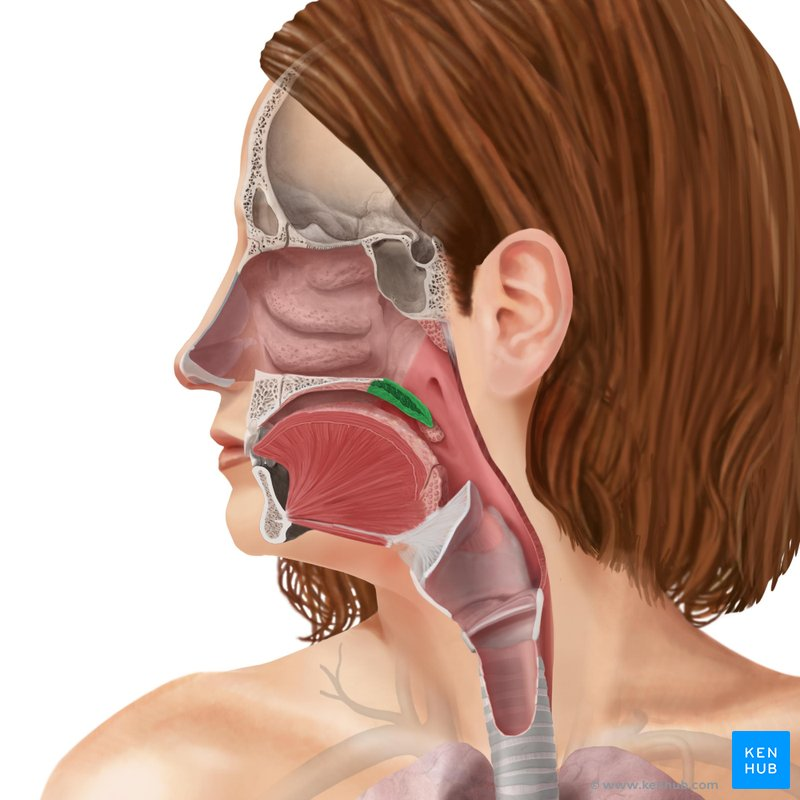

Nasopharynx

yellow highlight

Oropharynx

green highlight

Laryngopharynx

blue highlight